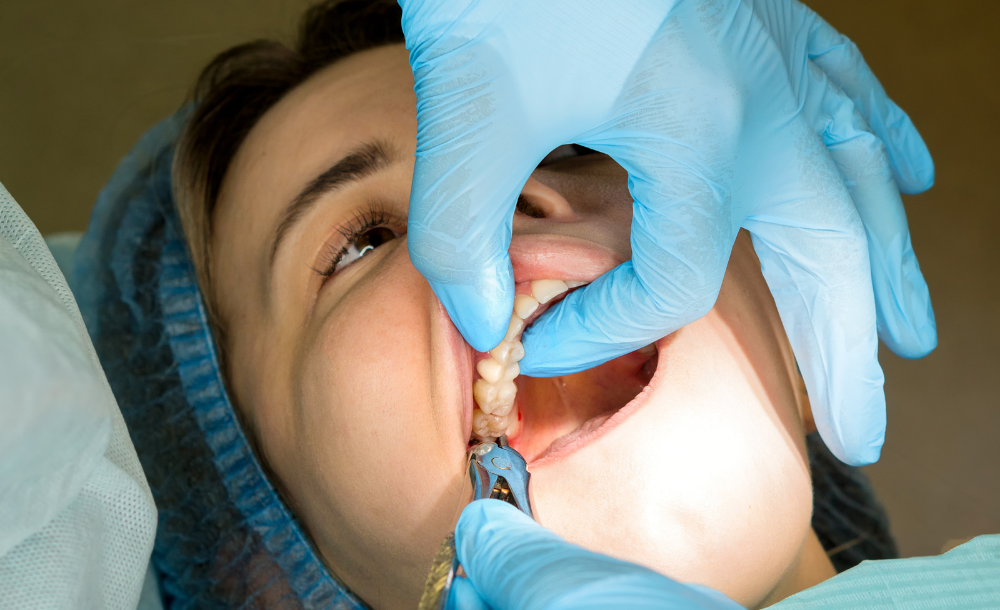

Wisdom teeth, or third molars, usually erupt between the ages of 17 and 25. In many cases, they can cause pain, crowding, infection, or damage to nearby teeth if there isn’t enough space for them to grow properly. At The Family Dental Clinics, we offer safe and comfortable wisdom teeth removal to protect your oral health and relieve discomfort.

Local Anesthesia / Sedation – Ensuring a pain-free experience

Gentle Extraction – Using advanced techniques for quick recovery